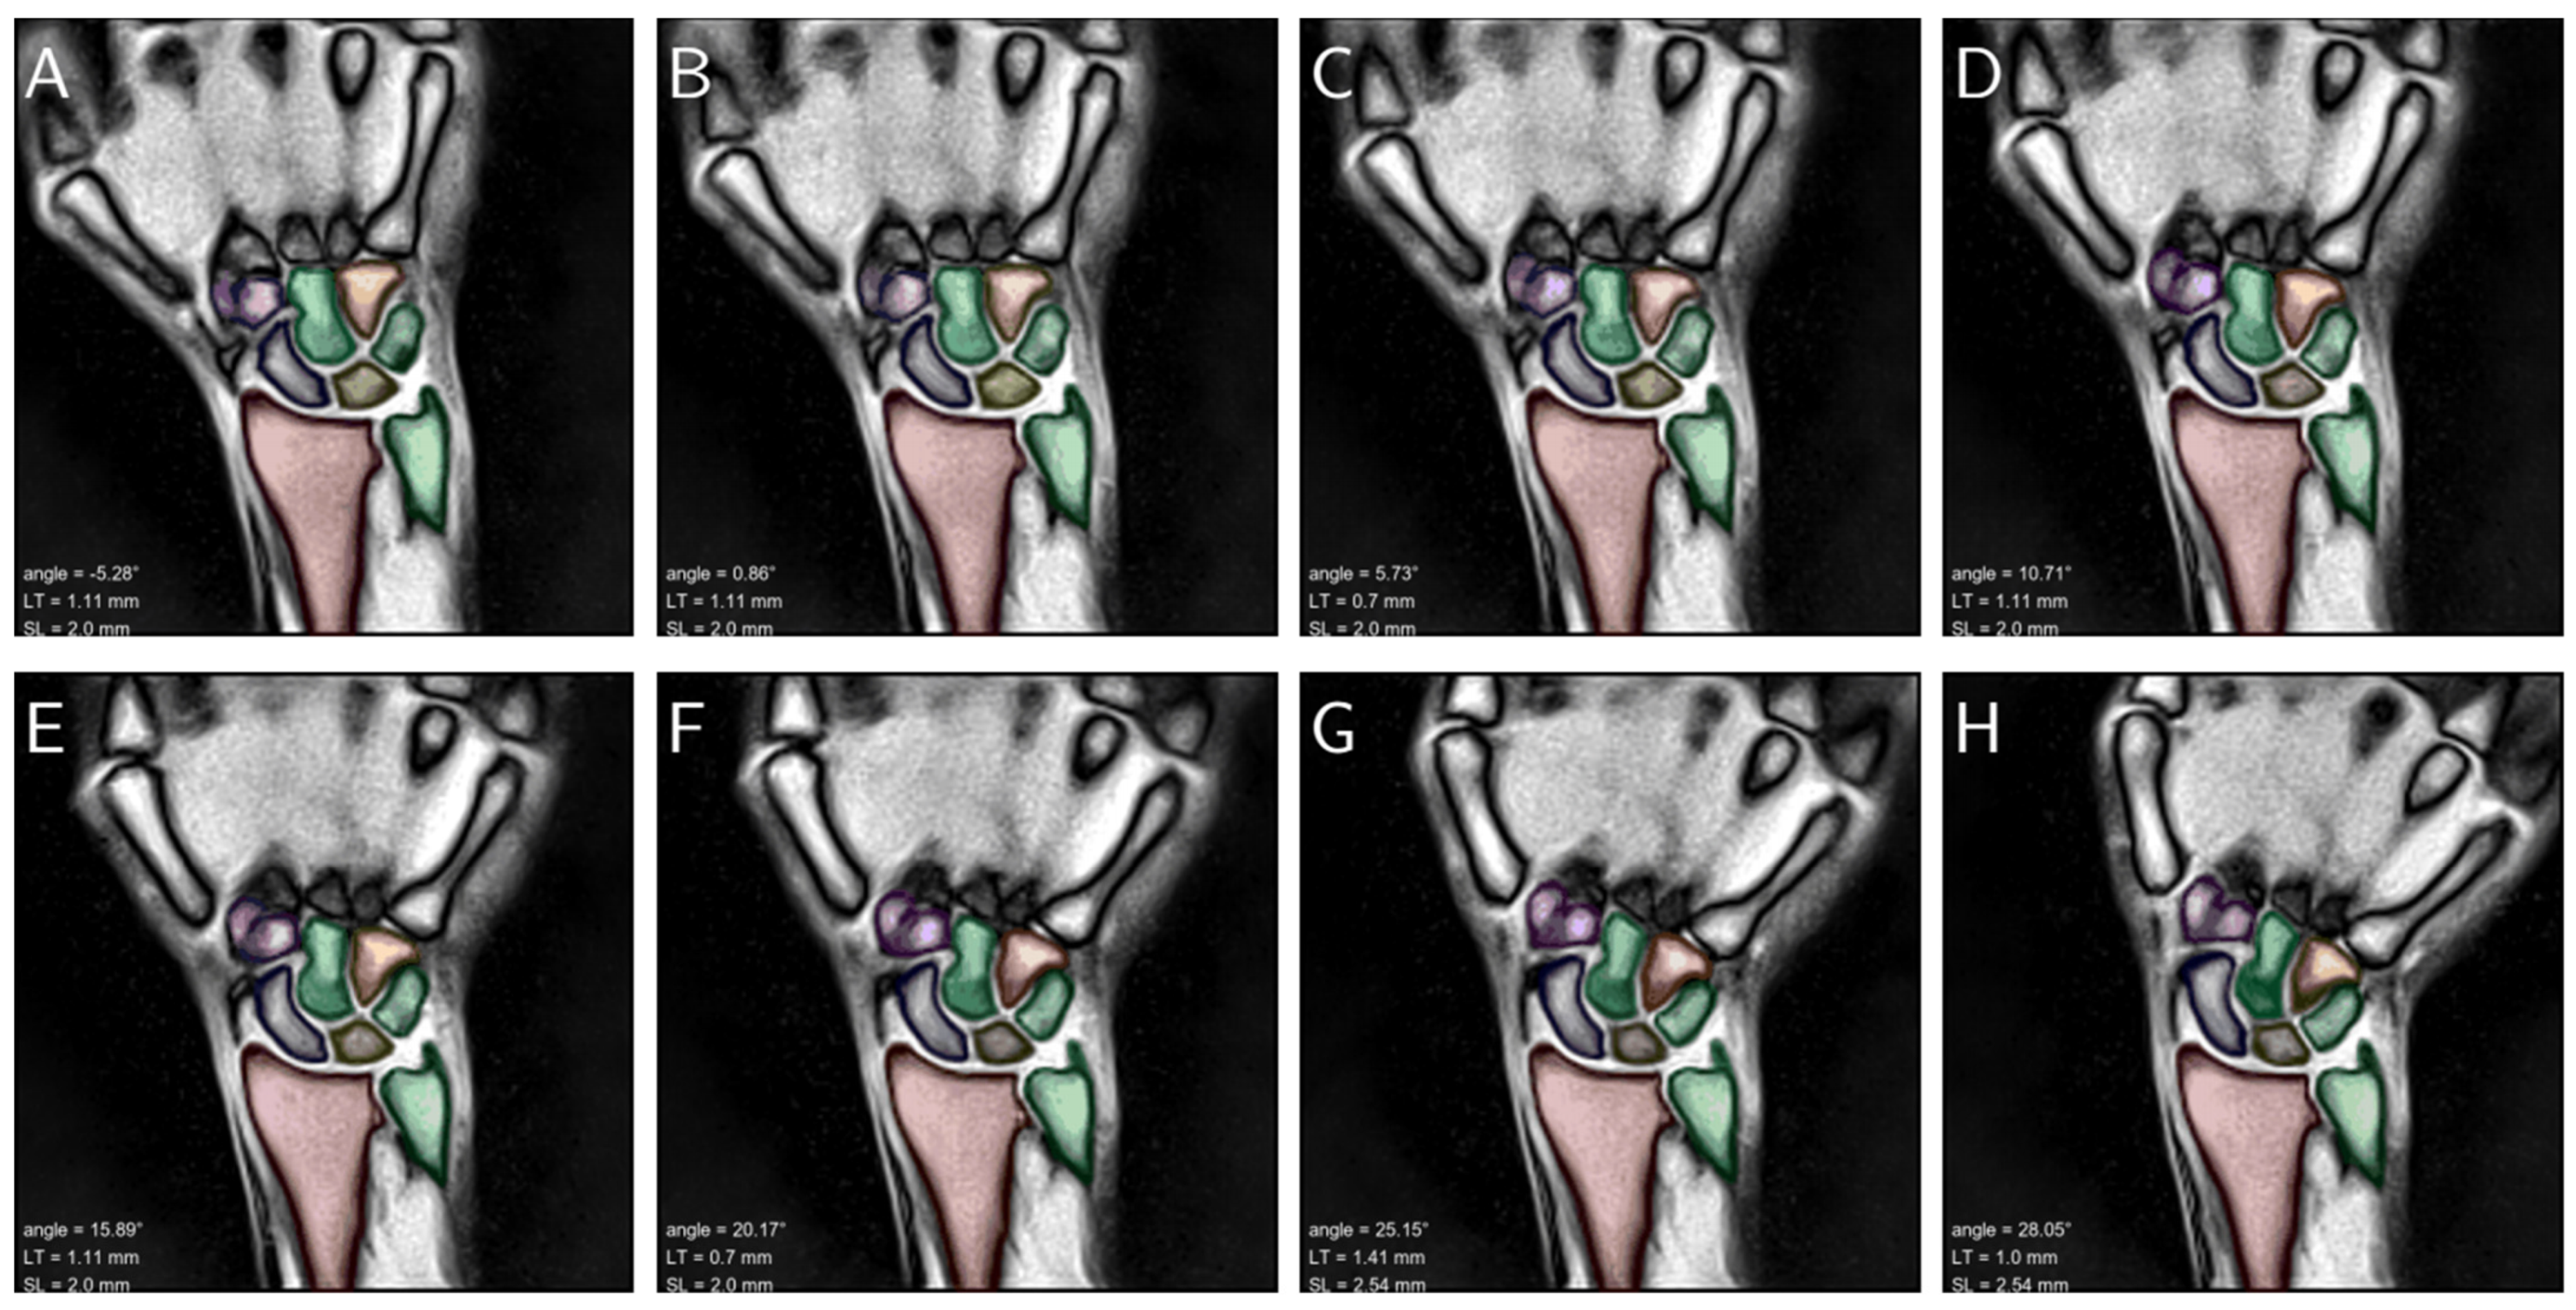

3.4. Assessment of Clinical Applicability in a Patient